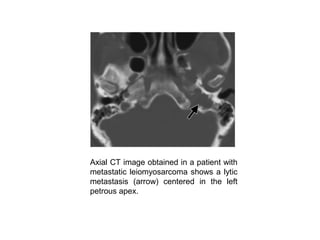

Axial CT image obtained in a patient with

metastatic leiomyosarcoma shows a lytic

metastasis (arrow) centered in the left

petrous apex.